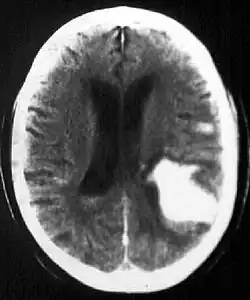

The exact process that leads to bleeding depends on the underlying cause. For intraparenchymal hemorrhage associated with hypertension, small holes in arteries are thought to cause bleeding in the deep penetrating arteries of the brain, which are smaller and thinner than other arteries. These are the arteries that supply blood to the basal ganglia, the thalamus, the brainstem, and deep portions of the cerebellum. Thus, these are the most commonly implicated structures in intraparenchymal hemorrhage associated with hypertension.[2]

Computed tomography (CT scan): A CT scan may be normal if it is done soon after the onset of symptoms. A CT scan is the best test to look for bleeding in or around your brain. In some hospitals, a perfusion CT scan may be done to see where the blood is flowing and not flowing in your brain.